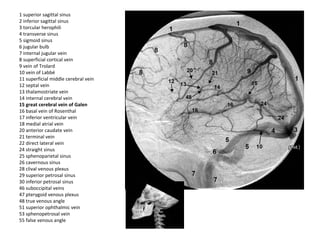

1 superior sagittal sinus

2 inferior sagittal sinus

3 torcular herophili

4 transverse sinus

5 sigmoid sinus

6 jugular bulb

7 internal jugular vein

8 superficial cortical vein

9 vein of Trolard

10 vein of Labbé

11 superficial middle cerebral vein

12 septal vein

13 thalamostriate vein

14 internal cerebral vein

15 great cerebral vein of Galen

16 basal vein of Rosenthal

17 inferior ventricular vein

18 medial atrial vein

20 anterior caudate vein

21 terminal vein

22 direct lateral vein

24 straight sinus

25 sphenoparietal sinus

26 cavernous sinus

28 clival venous plexus

29 superior petrosal sinus

30 inferior petrosal sinus

46 suboccipital veins

47 pterygoid venous plexus

48 true venous angle

51 superior ophthalmic vein

53 sphenopetrosal vein

55 false venous angle